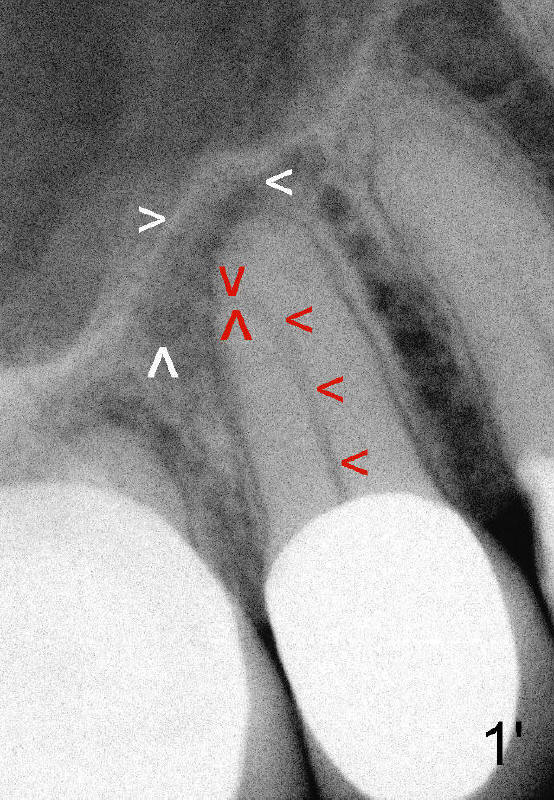

四十八岁俄国女人去年因右上牙痛就诊,右上五(图一:美国称为四号牙)有牙冠修复,叩诊疼痛,牙髓测定死髓牙,术前很难理解为什么根管末端弯曲(图一':红箭头;白箭头代表根尖阴影范围),根管扩大至40/.06(rotary file),插入同一号牙胶尖(图二箭头),好像挺接近弯曲根管顶端,但是离根尖还有一些距离,从牙冠打洞,里面一片漆黑,使用两倍半放大镜(loops),也无能为力,最后完成根管充填(图三),看上去挺不错,顺着弯曲根管走(箭头),有些得意洋洋,最末端部分(上下箭头之间)可能被糊剂充填。欣慰的是术后疼痛消失,一年后病人因右下桥松动而再次就诊,检查表明七断裂需要拔牙,植牙,由于下牙槽神经在根尖片中看得不清楚,她牙齿问题很多,便拍摄全口CT。右上五CT显示根尖阴影好像没有减少多少(图四箭头,与图一',图二,图三对比),所以根管末端弯曲有一定特殊意义,那是什么呢?